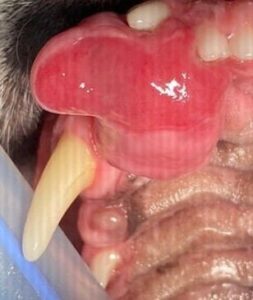

Images of the same tumor after rostral maxillectomy, including the fragment excised.

ย ย ย

Even extensive surgical procedures like a maxillectomy or mandibulectomy are well tolerated by dogs. Once they recover from anesthesia, they are able to go home, and most of them eat dinner the same night!ย

Cats are less tolerant of extensive surgeries, but with supportive care and assisted feeding, they can benefit from surgical treatment as well. A favorable outcome greatly depends on the staging of the tumor (type, size, lymph node involvement and metastasis at the time of diagnosis).